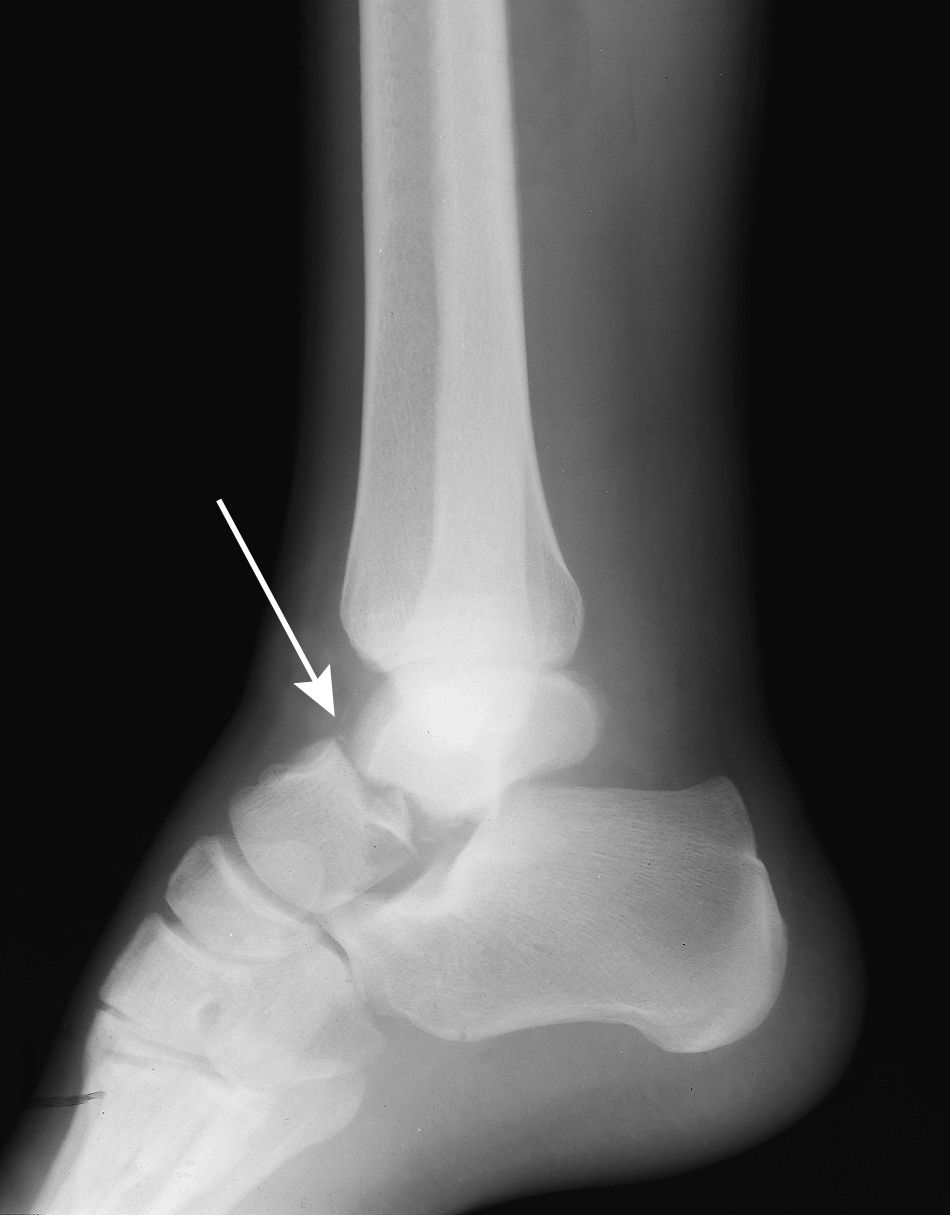

Most avulsion fractures heal very well without surgical intervention. Elevating the foot above the level of the heart helps to minimize swelling and pain. The talar avulsion fracture in this patient is also small with only slight displacement and is seen hovering just above the mid to anterior talus.